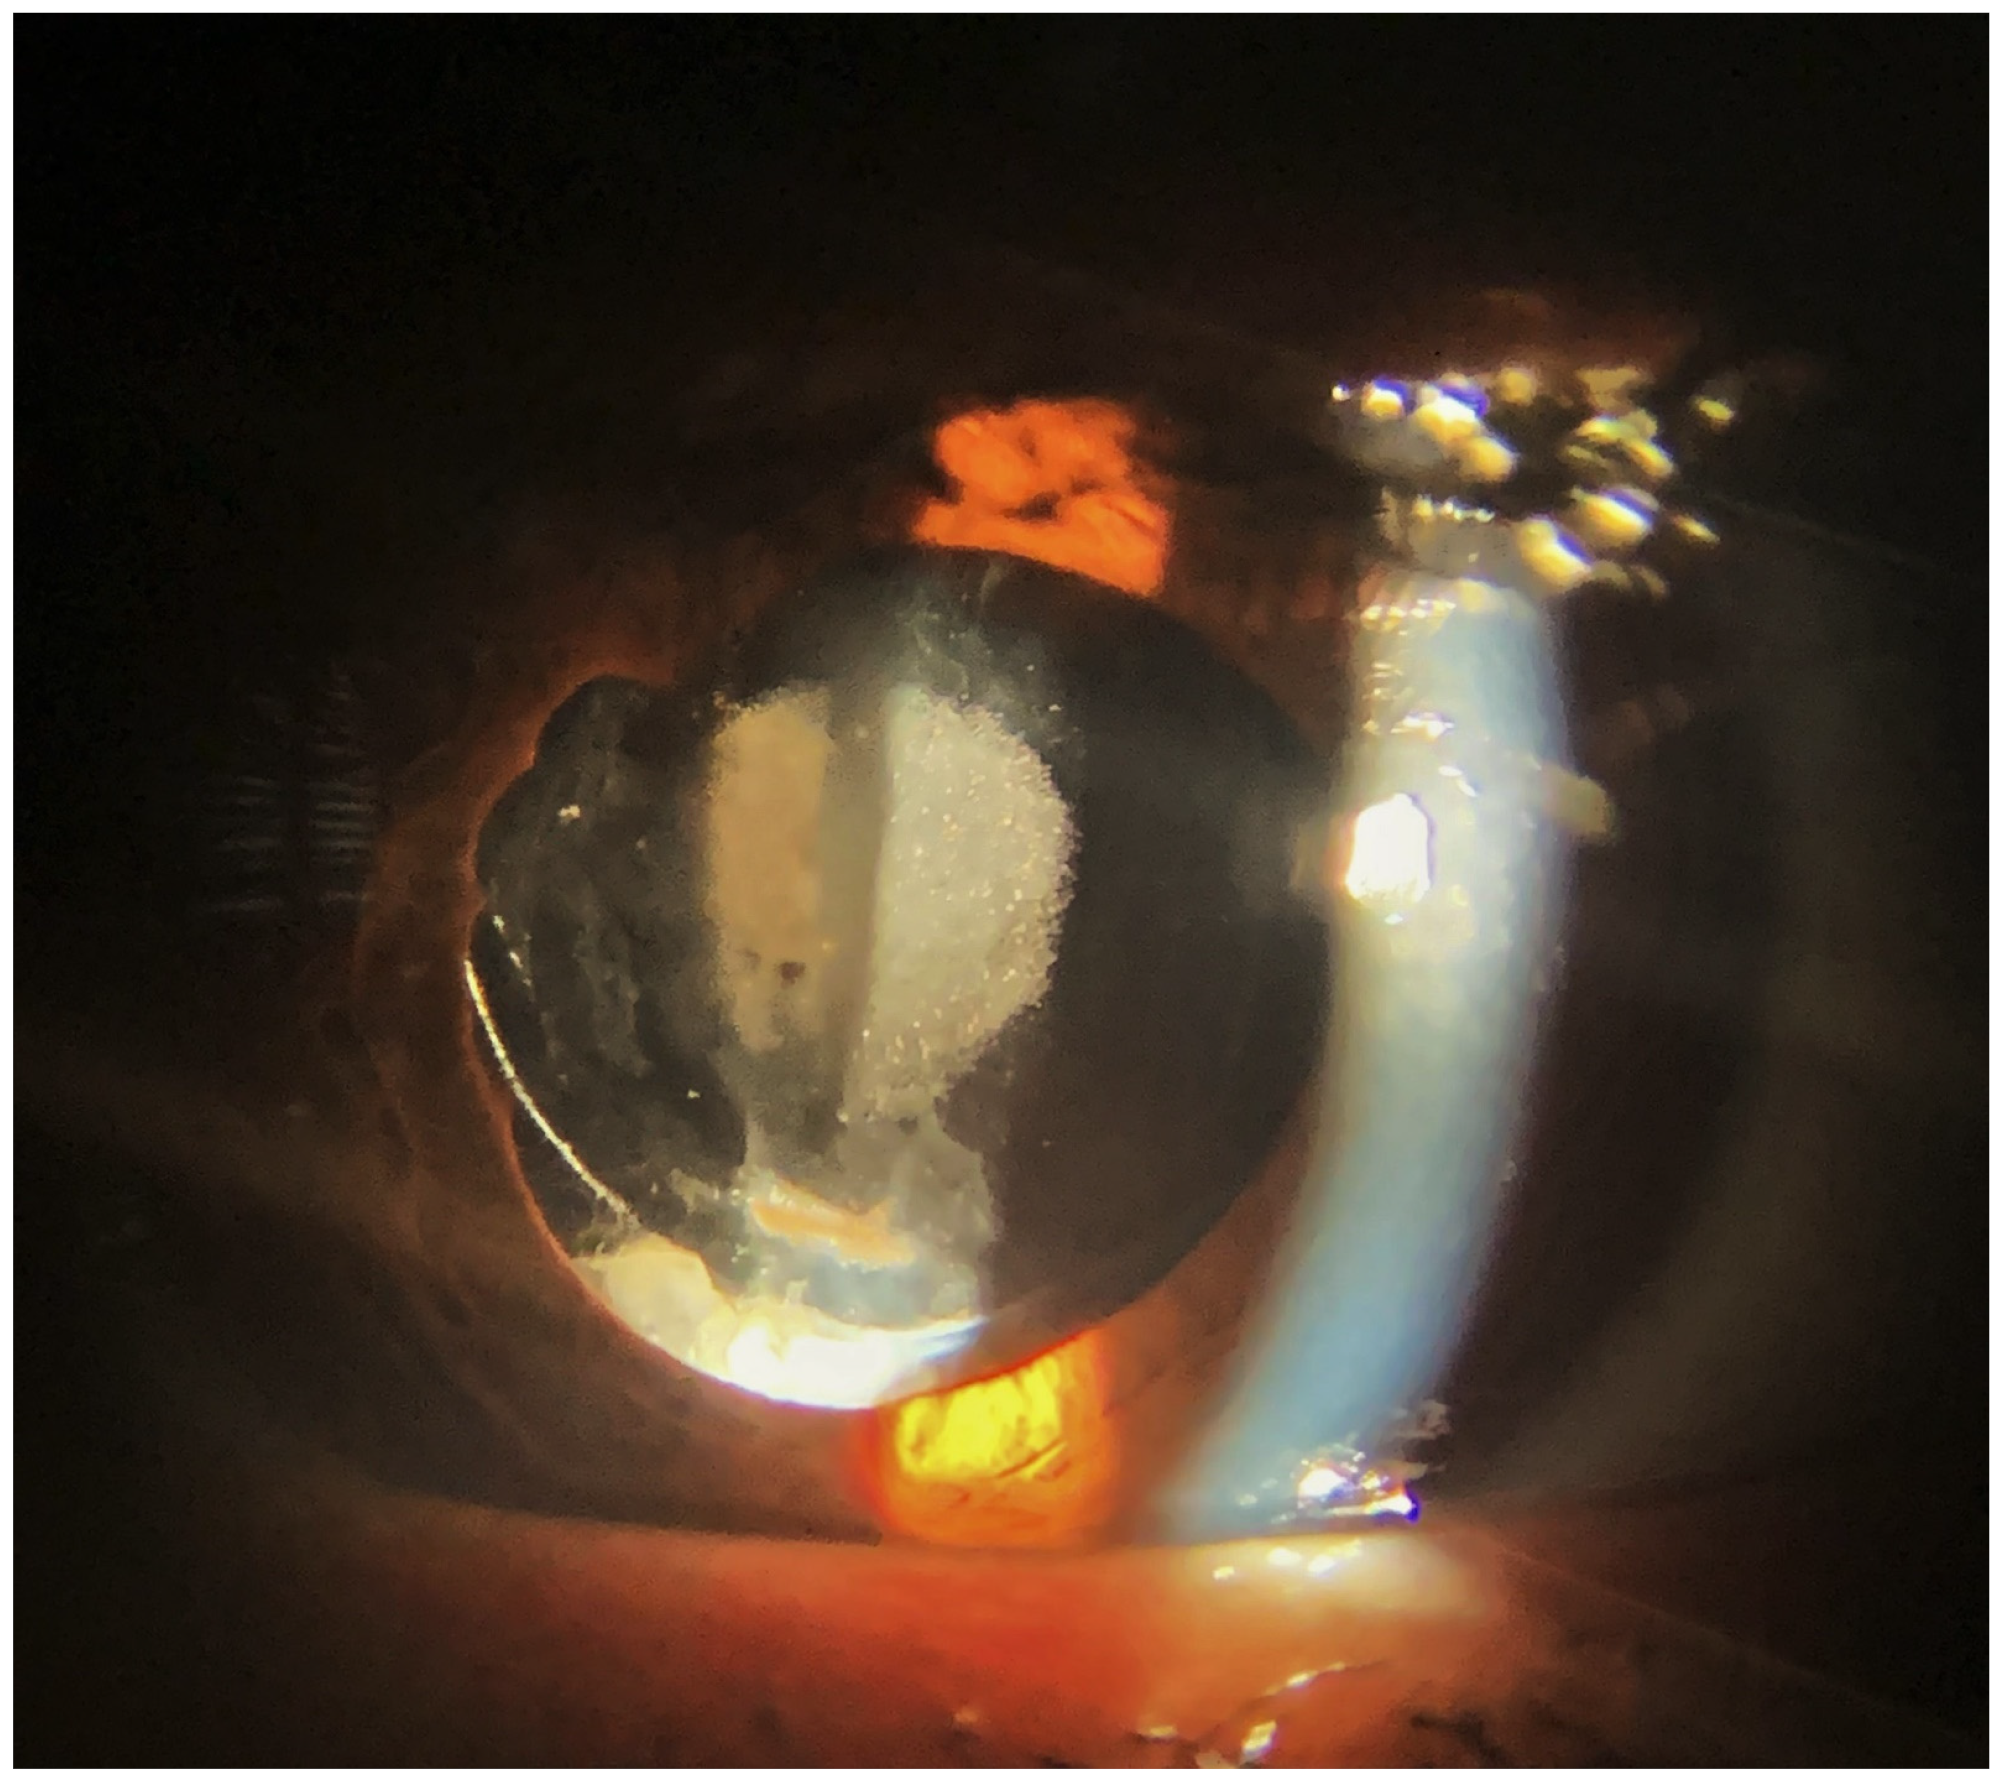

Central opacification of IOLs was demonstrated at the slit-lamp examination (Figure 1 and Figure 2). Nine of 14 IOLs (64.28%) had opacification at the anterior surface, and two of 14 IOLs (14.28%) had opacification at the posterior surface. The David J Apple International Laboratory for Ocular Pathology examined and identified calcium phosphate deposits in all IOLs located within the pupillary area, always sparing the haptic and sometimes the peripheral optic (Figure 3).

Figure 2.

Pre- and intraoperative findings of two eyes that needed IOL exchange for dense IOL calcifications. Phaco-vitrectomy with C2F6-gas was performed for retinal detachment using an AcriSmart IOL (previous Acri.Tec, now Zeiss Asphina) (A,B—case 4) and Basis Z (1st Q, Mannheim—case 11) (C,D). Note that the deposits are located in the pupillary area, but the haptics are spared.